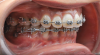

Fig 8. A class III adult male patient required surgical orthodontic treatment. The patient had anterior and posterior crossbites and required leveling of a deep curve of Spee during presurgical orthodontics.

Figure 8

Fig 9. A class III adult male patient required surgical orthodontic treatment. The patient had anterior and posterior crossbites and required leveling of a deep curve of Spee during presurgical orthodontics.

Figure 9

Fig 10. A class III adult male patient required surgical orthodontic treatment. The patient had anterior and posterior crossbites and required leveling of a deep curve of Spee during presurgical orthodontics.

Figure 10